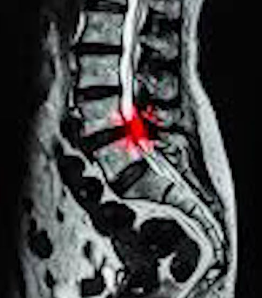

척추협착증 진단

척추협착증 진단, CT와 MRI 촬영 등을 통해서 척추관 크기와 주변 관절과 인대, 추간판의 상태를 알아보고 종합적으로 진단을 하게 됩니다. 근전도 검사와 신경전도 검사도 함께 병행해서 하게 되겠습니다.